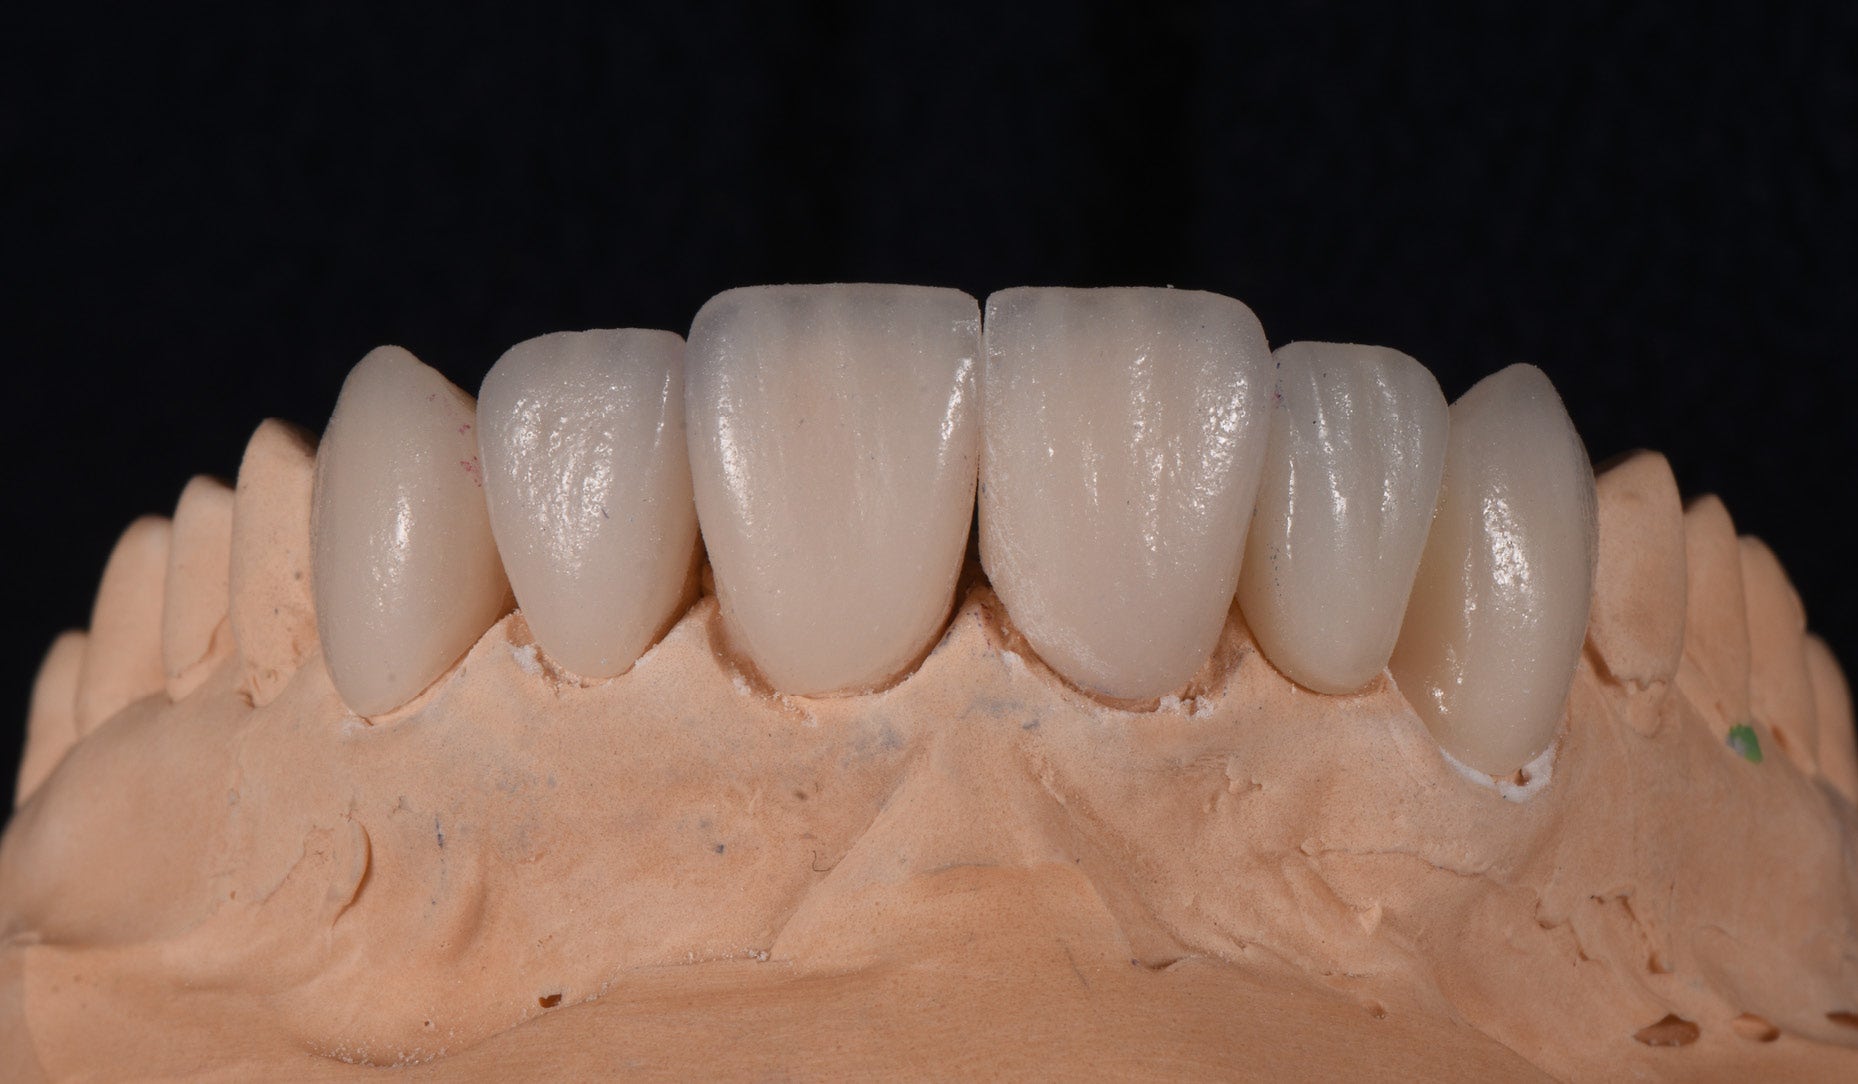

Clinical Cases, Labside Two high-strength ceramics, one micro-layering system Case by DT Andreas Chatzimpatzakis AESTHETIC AND EFFICIENT SMILE MAKEOVER Most patients asking for a smile makeover desire custom solutions rather than an off-the-peg smile: Individual tooth shapes that fit their face and their character, an internal play of colours that matches their age and natural dentition. Modern dental materials allow us to deliver what they demand in many situations – usually at a reasonable price. For a long time, however, we have been facing challenges when combining cosmetic and medically indicated treatment – e.g. a smile makeover including the rehabilitation of a missing lateral incisor. A straightforward solution – using lithium disilicate veneers alongside a zirconia cantilever bridge, both finished with their respective porcelain systems – would have been complicated by potential differences in the final appearance. With CERABIEN™ MiLai (Kuraray Noritake Dental Inc.), a set of internal stains and porcelains designed for micro-layering, the situation is different: Suitable for micro-layering on zirconia and lithium disilicate, it supports its user ideally in creating a harmonious smile even when the two framework materials are combined. A NEW CUSTOM SMILE The following patient case is a perfect example: A female patient with a missing lateral incisor, multiple visible composite restorations in the anterior region and an enamel fracture at her incisal edge desired a smile makeover. The selected materials were Amber Press LT (HASS), shade A1, for four veneers on the central incisors and the left lateral incisor and canine (teeth # 11, 21, 22 and 23 according to the FDI notation) and KATANA™ Zirconia YML (Kuraray Noritake Dental Inc.), shade A2, for the planned cantilever bridge on the maxillary right canine, replacing the missing lateral incisor (teeth # 12 and 13). Fig. 1. Female patient with a missing maxillary lateral incisor and multiple composite restorations in the anterior area – a smile makeover is desired. Fig. 2. Patient with mock-up. Fig. 3. Minimally invasive preparation through the mock-up, which takes into account the minimum space required for the planned materials and restorations. Fig. 4. Teeth prepared for the all-ceramic restorations. Fig. 5. Occlusal view of the maxillary teeth after tooth preparation. Fig. 6. Full-contour veneers and cantilever bridge on the model. Fig. 7. Restorations after a cutback limited to the vestibular and incisal area. Fig. 8. CERABIEN™ MiLai LT1 is applied to the middle and cervical area of the zirconia cantilever bridge. Fig. 9. CERABIEN™ MiLai Value Liner 2... Fig. 10. … and Value Liner 1 applied to the incisal area of the central and lateral incisor restorations. Fig. 11. CERABIEN™ MiLai porcelain Creamy Enamel mixed with Value Liner 2 (70/30) added to the middle and cervical areas of the four lithium disilicate restorations to increase and control the value. Fig. 12. ... while E2 is added to the incisal area of both canines. Fig. 13. Restorations covered by a layer of Tx ... Fig. 14. ... and LTx. Fig. 15. Appearance of the restorations after the first bake. Fig. 16. Adding translucency and opalescence to the cervical area with LT1 and brightness to the ridges with Creamy Enamel. Fig. 17. Completion of the enamel surface with a cover layer of LTx, which is responsible for a high translucency and opalescence. Fig. 18. Result of the second bake. Fig. 19. Final restorations with a natural self-glaze effect on the model. Fig. 20. Final restorations with a natural self-glaze effect in the patient’s mouth. Fig. 21. Smooth optical integration of the restorations. Fig. 22. Beautiful treatment outcome. CONCLUSION With the described approach and selected materials, it was possible to create restorations with a natural shade, shape and texture. They matched not only the appearance of the remaining natural teeth, but also showed internal consistency across the selected framework materials. The technical procedure was quite straightforward and efficient, while the result speaks for itself. Special thanks to Dr. Kanellos Ioannis for the collaboration on this case and for kindly providing the pre- and post-treatment photographs that complemented it. Dental technician: ANDREAS CHATZIMPATZAKIS Based in Athens, Greece, Andreas Chatzimpatzakis is the founder and director of ACH Dental Laboratory (since 2000), specializing in refractory veneers, lithium disilicate, zirconia, and implant prostheses. He graduated in Dental Technology from the University of West Attica and received advanced training in all-ceramic restorations in Helsinki and Japan under renowned masters including Shigeo Kataoka. Since 2017, he has served as an international trainer for Kuraray–Noritake Dental Inc., delivering lectures and hands-on courses worldwide on advanced ceramic techniques. He has also held roles as Key Opinion Leader for MPF Brush Co., Ambassador for Hass Co., and Editor-in-Chief of Laborama. An active member of the Hellenic Academy of Aesthetic Dentistry, his work and articles have been published in both Greek and international journals. Jan 21, 2026 Dental Technician Kuraray Noritake Prosthodontics Clinical Case Katana Zirconia YML CERABIEN MiLai Prosthetic dentistry Lab Dental Ceramics Cad Cam Discs KATANA Zirconia YML View Product CERABIEN MiLai View Product Subscribe to our Newsletter Join thousands of dental professionals and receive free advice that can help you and your career. We will not spam or share your e-mail.